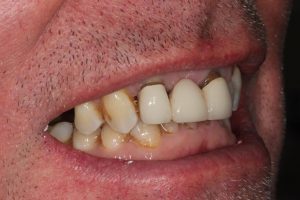

This patient had broken their upper front tooth and the exisitng dental crown had fallen off. The underlying root was unfortunatley irreparable.

The dental root was subsequently removed and an implant placed at the same time. The implant had a temporary crown placedon the same day.

The ‘After’ photos shows the final crown that was made after 3 months. The implant crown was made to match the form and colour of the exisiting teeth to give an overall natural aesthetic finish.